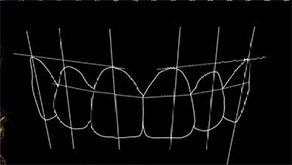

[ DSD��������6������ ]

DSD����

[ DSD��̬�������������� ]